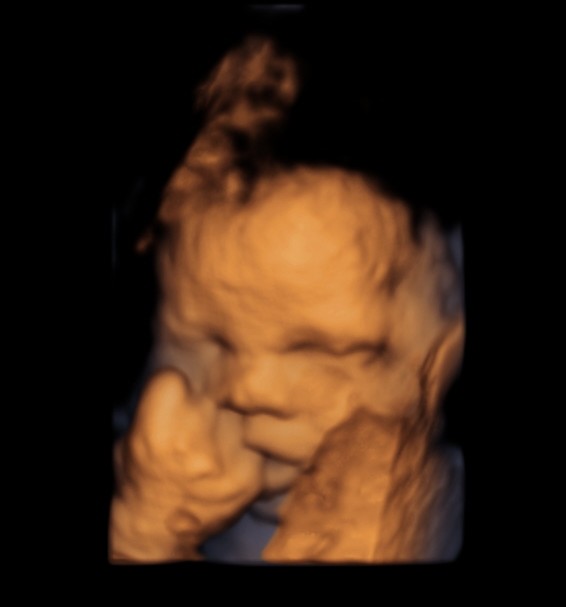

BABY FACE ( Just for fun ) Date: May 25, 2014Author: kriznan Category: 3 d images, fetal face, Fetal Ultrasound, ultrasound images Tags: baby face 3 d images, baby sucking finger, baby yawning Post navigation ← HEMANGIOMA OF THE LIVER IUGR OR SKELETAL DYSPLASIA OR RENAL DYSPLASIA → This is just an intermediate filler . enjoy the expressions. Thinking Yawning or just putting out the tongue Sucking the fingers Wondering So , what is lost now ? ok Papparazi ! enough for the day . go away. Share this: Share on X (Opens in new window) X Share on Facebook (Opens in new window) Facebook Email a link to a friend (Opens in new window) Email Share on LinkedIn (Opens in new window) LinkedIn Share on WhatsApp (Opens in new window) WhatsApp More Print (Opens in new window) Print Share on Reddit (Opens in new window) Reddit Share on Tumblr (Opens in new window) Tumblr Share on Pinterest (Opens in new window) Pinterest Share on Telegram (Opens in new window) Telegram Like Loading...